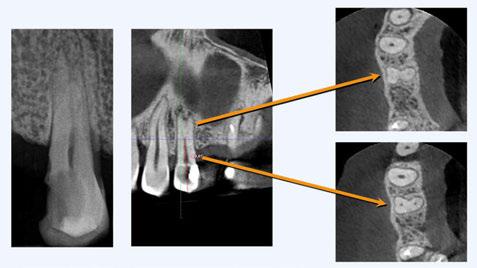

Este caso clínico es un premolar que tiene 3 conductos: sabemos que 2 de ellos son en la raíz vestibular, y

en el CBCT podemos apreciar a qué longitud del conducto se produce la bifurcación (Figura 10)

Debido a la gran curvatura que se produce en la bifurcación, tenemos que precurvar los instrumentos manuales y rotatorios, para facilitar que los instrumentos alcancen la LT (Figura 11). Terminamos el conducto mesiovestibular y palatino en conicidad .06 y el disto-vestibular en .04 debido al riesgo que pensamos que correríamos si hacemos una secuencia más amplia.

Valorando cada uno de los factores que hemos descrito anteriormente, podemos decidir, para el éxito de este tratamiento, una combinación: secuencia más progresiva; trabajar 3 ciclos por conducto para los instrumentos de preinstrumentación y conformación; eliminación de interferencias coronales con puntas ultrasónicas

e instrumento 25.09; terminar en conicidad .04/.06 según la dificultad del conducto; combinar movimiento continuo y alterno; y usar instrumentos precurvados de manera manual previo al rotatorio. Todo esto hará que resolvamos este caso clínico de manera satisfactoria (Figura 12). ●

Figura 10. Estudio Radiográfico en 2D y 3D del caso clínico. Figura 11. Secuencia operatoria que realizamos en cada uno de los conductos. Figura 12. Secuencia realizada para la obturación con onda continua.